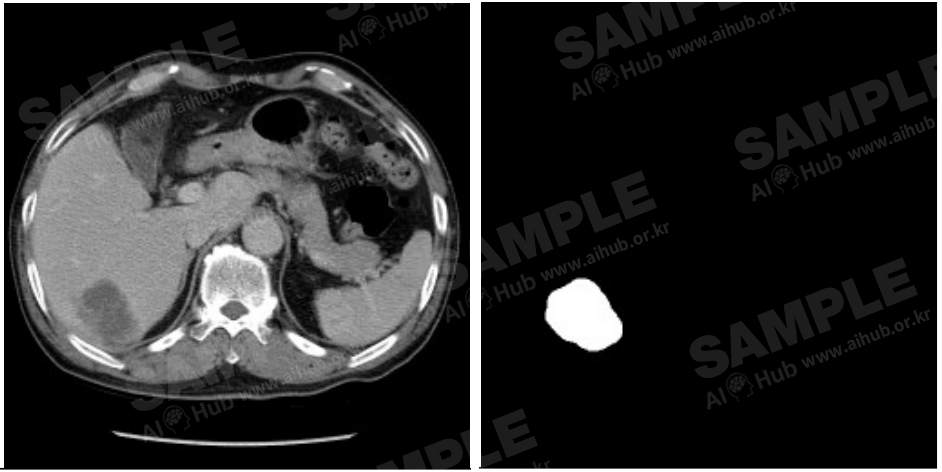

간암 진단 및 치료 과정에서 필요한 영상‧이미지 데이터

- 구축량 : 1,854,269

간암 진단 및 치료 과정에서 필요한 의료 이미지 데이터셋 구축 의료 영상의 판독 결과와 진단 및 치료에 영향을 주는 임상 정보 등을 어노테이션한 학습용 데이터셋 구축 구축된 AI데이터를 이용하여 의료 단계별 의사결정에 직간접적 영향을 줄 수 있는 AI모델 제시

대표도면